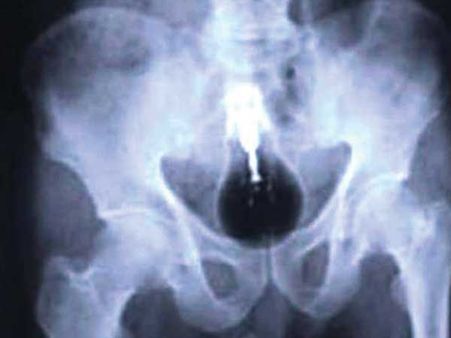

લાઇટ બ્લબ

એક પાકિસ્તાની કેદીના પેટમાંથી મળ્યો લાઇટ બ્લબ. હવે આ ત્યાં કેવી રીતે પહોંચ્યો તે પણ વિષે વિચારીને તો ડોક્ટરનો પણ આશ્ચર્યચકિત થઇ ગયા હતા.